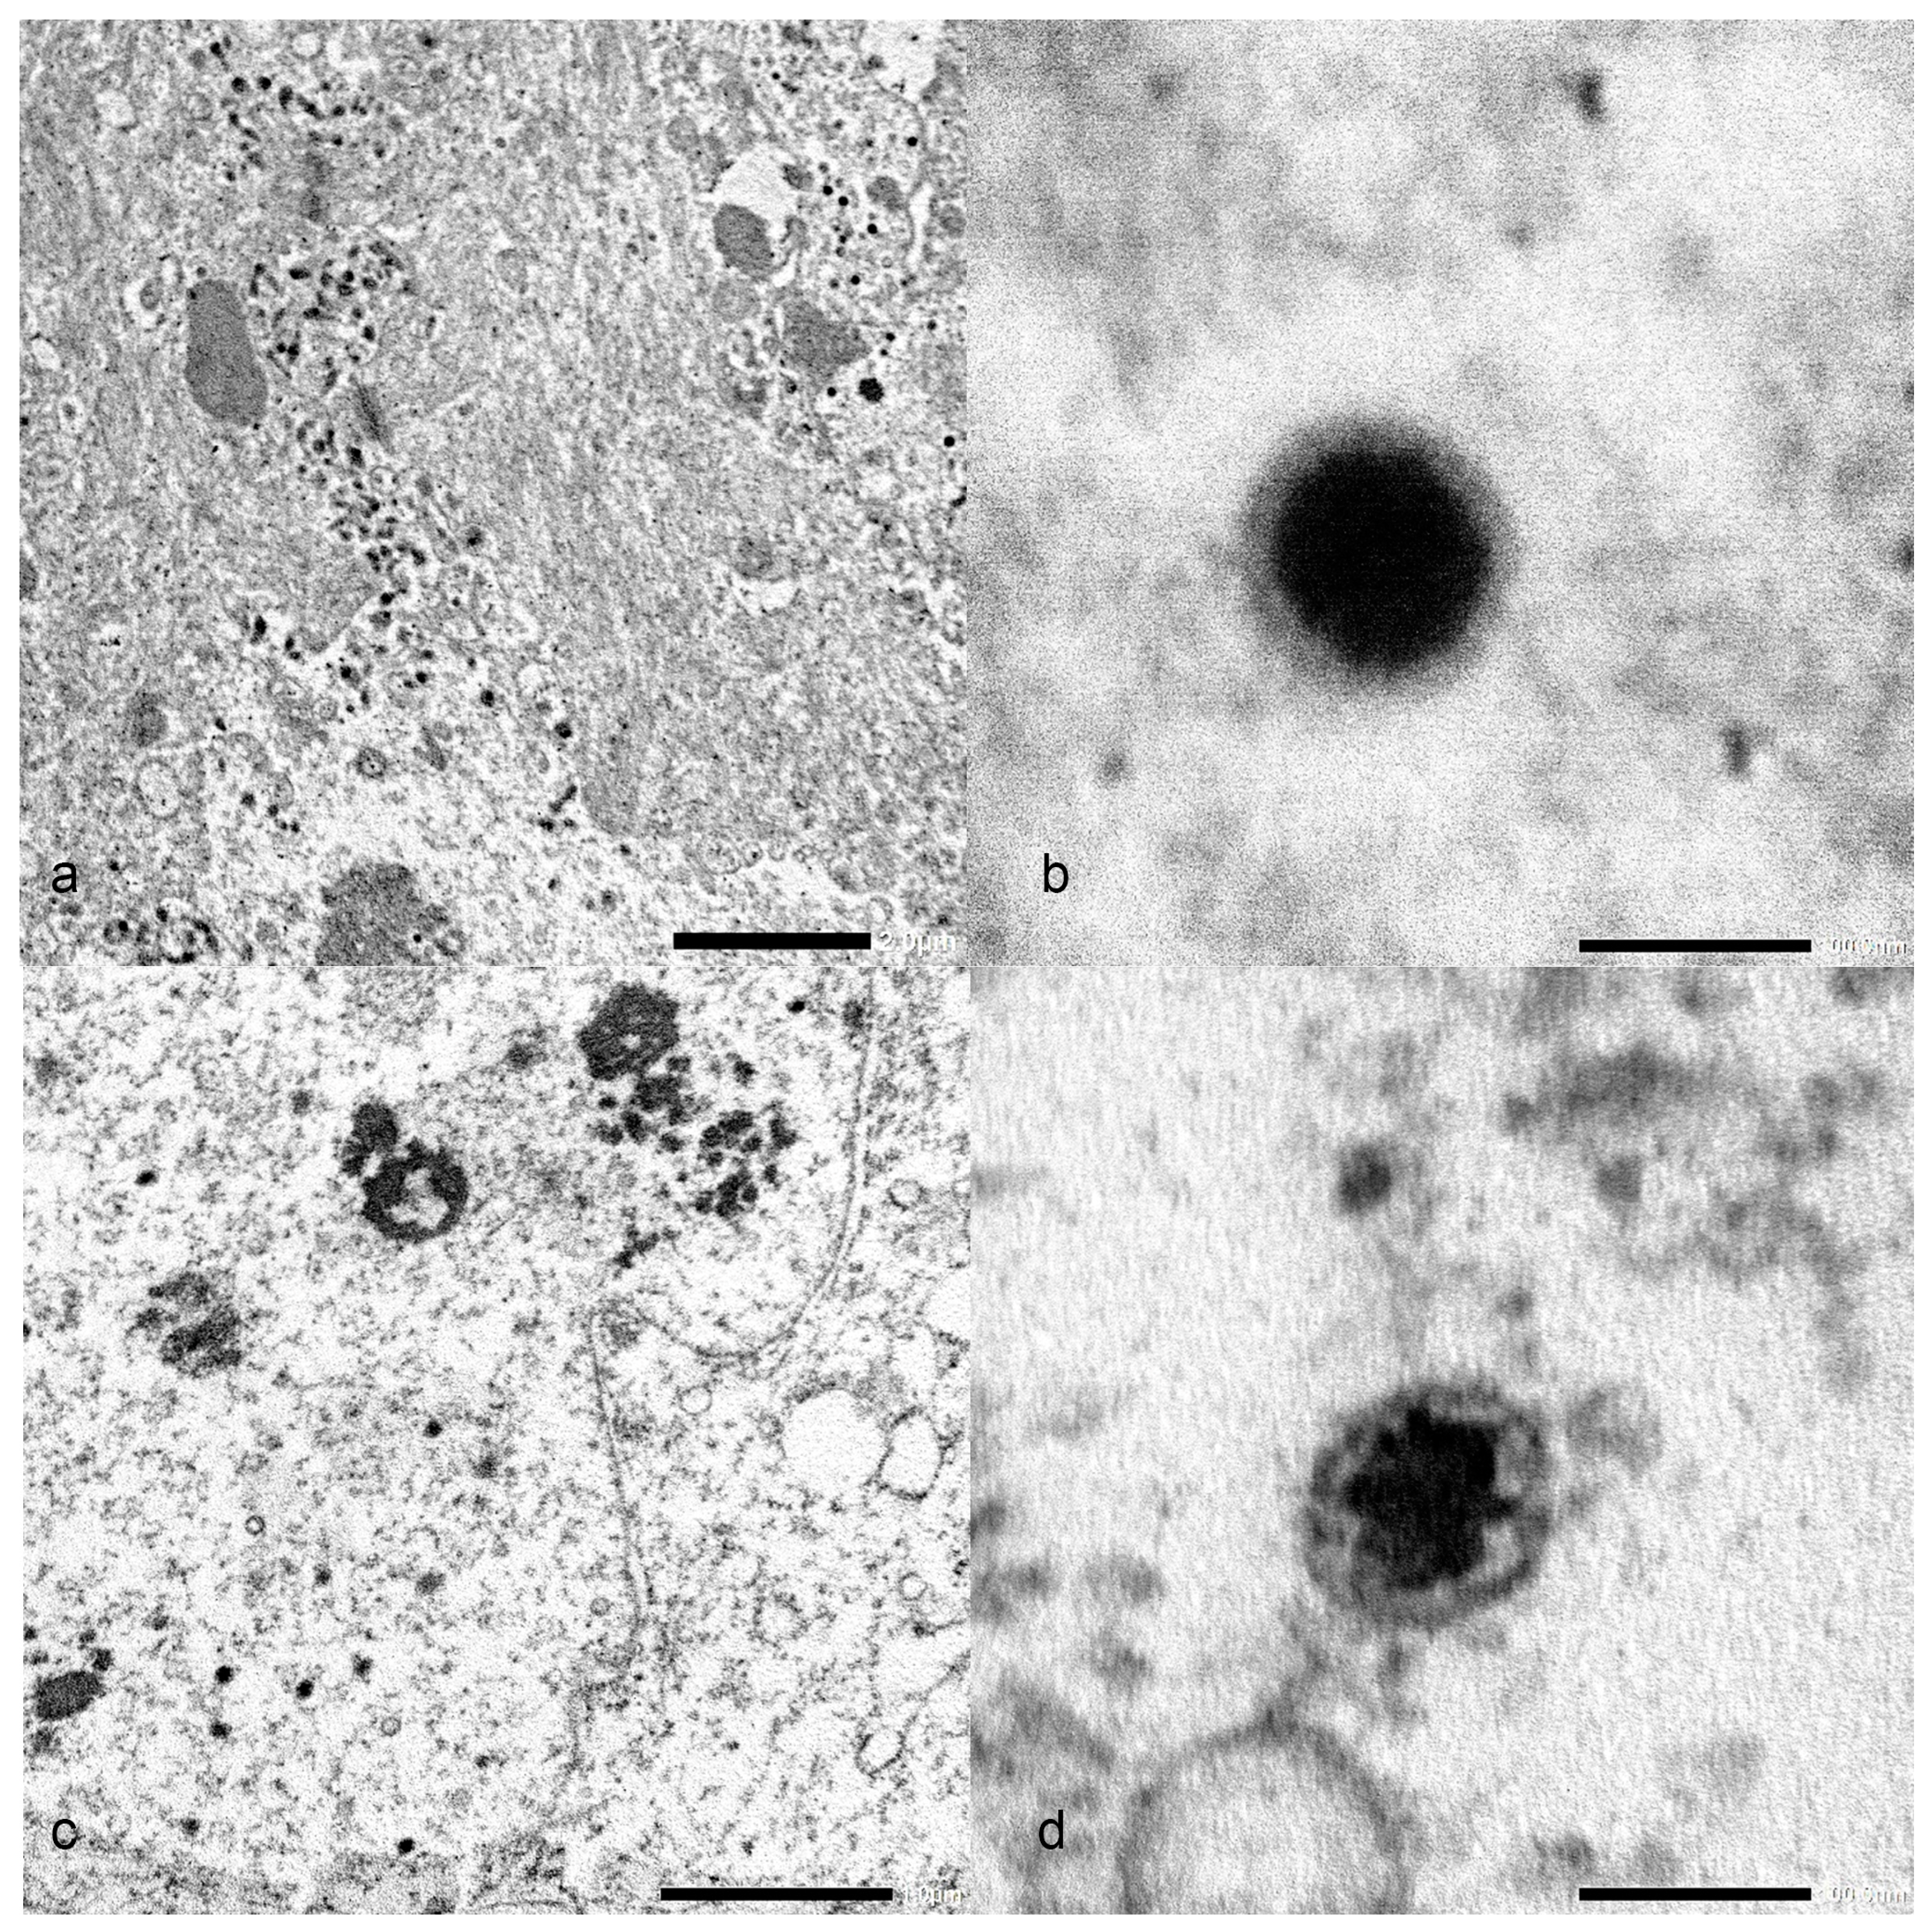

3.5. Electron Microscopy